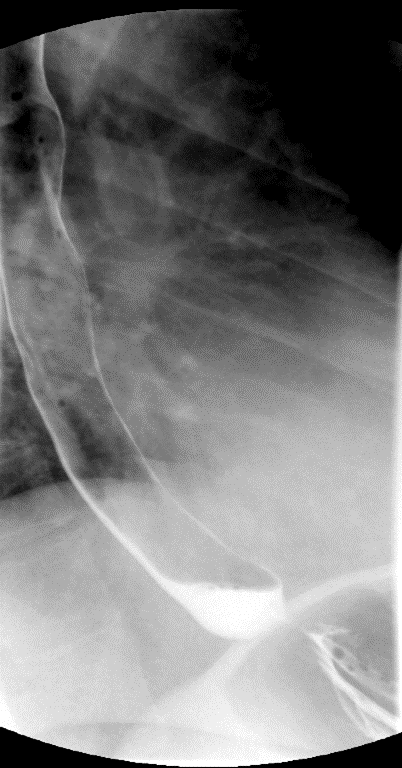

- Method—Thoracic:

- With the patient standing upright, have them turn into a left posterior oblique position.

- Instruct the patient that you will be handing them a cup containing a small amount of water and effevescent crystals and that they should drink it as quickly ask possible.

- As soon as the patietn has finished the water, exchange the empty cup for a cup of thick barium.

- Ask the patient to drink two (2) sips of thick barium. The patient does not need to drink this quickly.

- After the patient has begun drinking, take images of the upper and lower esophagus distended and coated with barium

(key image 5)

(key image 6)

(key image 7).

- Have the patient turn into the right posterior oblique position.

- Repeat steps 3 and 4, only this time the patient will take the barium in their right hand

(key image 8)

(key image 9)

(key image 10).

- Thoracic images are obtained in the upright RPO and LPO projections after the adminstration of bubbly barium (EZ Gas followed by thick barium).

- The goal of these images is to see the thoracic esophagus distended and coated with barium. This may not be possible with one image and make take several to accomplish.